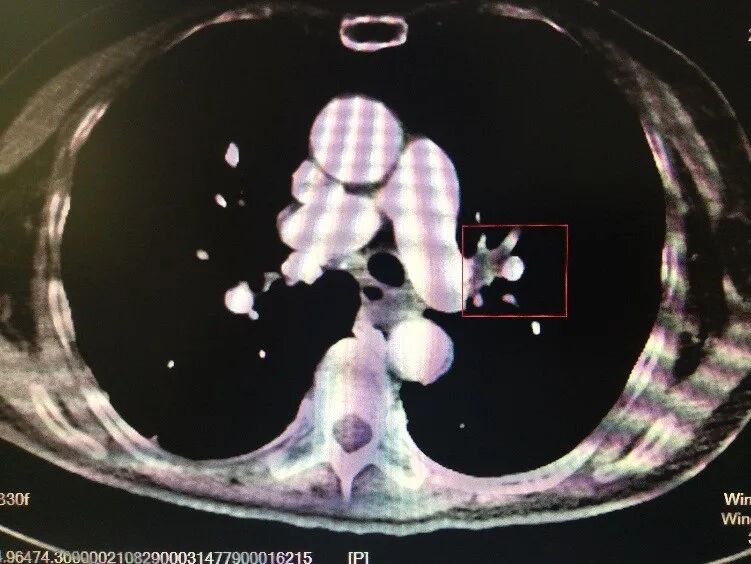

為了弄清原因,待鄧娭毑病情稍稍穩(wěn)定后在轉運呼吸機的支持下完善了頭胸腹CT+肺部CTA檢查,這時真正的“兇手”才浮出水面。

▲鄧奶奶的CT影像

“急性肺栓塞”